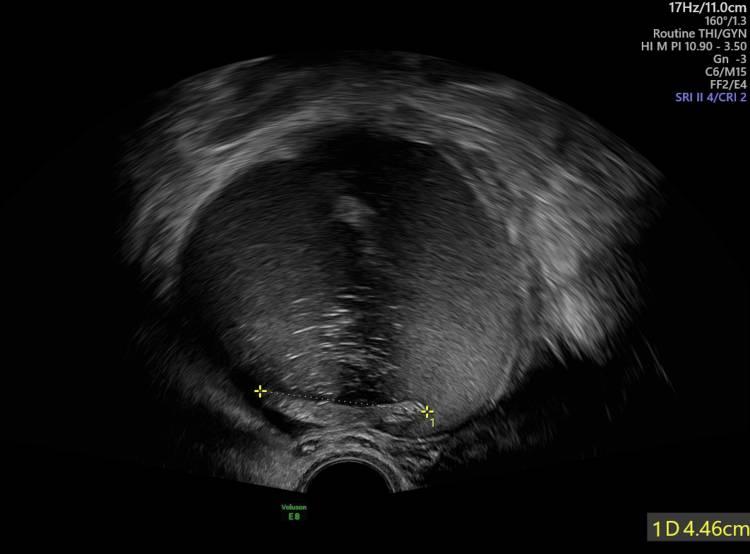

一位62岁的女性因腹痛和发热就诊。人病史包括过敏性哮喘、血脂异常和阑尾切除术。在临床检查期间,触诊了源自右卵巢的腹部肿块,这一发现最初是通过腹部超声发现的,被描述为右卵巢解剖区域直径为12厘米的异质结构。超声特征提示恶性肿瘤的可能性(图1)。

图1 腹部超声显示直径为10cm的肿块